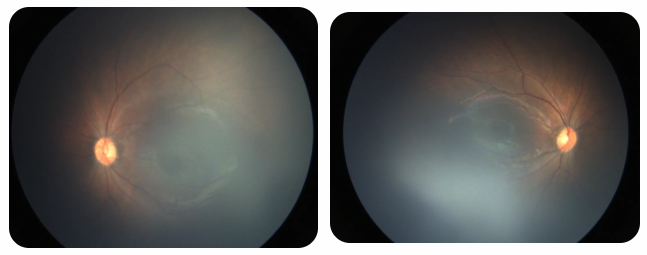

近期術前檢查:

術后復查:

廈門眼科中心黎曉新名醫(yī)工作室曾接診一名31周出生的早產兒,出生體重僅1300克。由于家長缺乏篩查意識,直到孩子5個月大時眼睛仍不會追光,才前來就診。檢查發(fā)現,患兒ROP已進展至4B期,因纖維血管增殖牽拉導致視網膜脫離,錯過了最佳治療窗口。盡管黎曉新教授團隊成功實施了玻璃體切割手術,孩子的視力仍存在不可逆損傷。此后,孩子開啟了長期隨診復查、治療的“護眼征程”,目前其右眼矯正視力為0.6,左眼為0.8。

相比之下,另一位早產寶寶在出生5周后,生命體征穩(wěn)定之時,便在產科醫(yī)生的建議下轉診至廈門眼科中心。經篩查確診為Ⅲ期ROP,黎曉新教授團隊及時為其進行了激光治療。半年后復查顯示,寶寶的視網膜血管發(fā)育正常,視力發(fā)育與足月兒童無異。